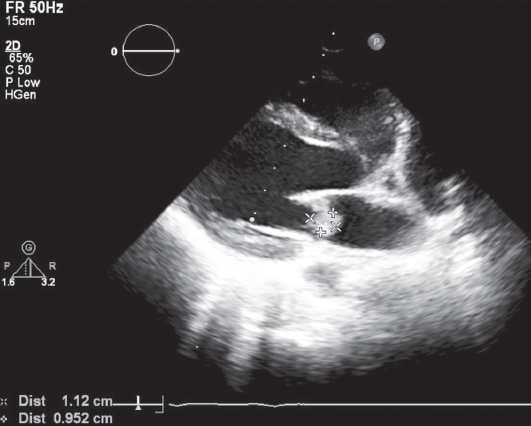

Чреспищеводная ЭхоКГ: визуализирована большая вегетация, длиной более 1 см, фиксированная своим основанием к задней сворке МК и вегетации на передней створке МК (рис. 5, 6).

Рис. 5. Чреспищеводная эхокардиограмма пациентки А., 16 лет. Продольная ось сердца. Стрелками указаны вегетации на задней створке митрального клапана

Fig. 5. Transesophageal ECHO of 16-year old female patient A. Long axis. Arrows indicate vegetations on the mural leaflet of the mitral valve

Рис. 6. Чреспищеводная эхокардиограмма пациентки А., 16 лет. Поперечная ось сердца. Стрелками указаны вегетации на задней створке митрального клапана

Fig. 6. Transesophageal ECHO of 16-year old female patient A. Short axis. Arrows indicate vegetations on the mural leaflet of the mitral valve